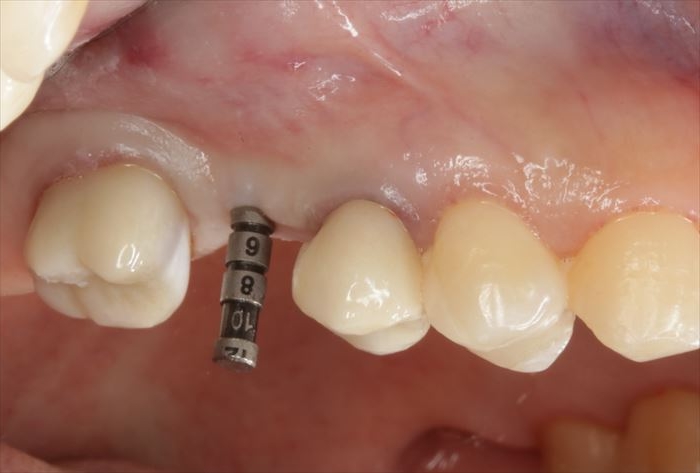

いよいよ本日インプラント埋入オペを行います。

まずはサージカルステントの適合を確認します。

修正が可能な深さまでドリリングして、深度ゲージを挿入してデンタルレントゲン写真を撮影します。

デンタルレントゲン写真において想定通りの角度であることから、ドリリングのステップを進めます。